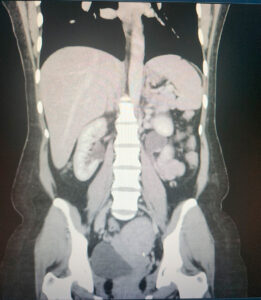

A 48-year-old woman presented with abdominal pain, fever (40.3 °C), nausea, and vomiting three days after undergoing hysteroscopic transcervical resection of a submucosal fibroid. Laboratory investigations showed a white cell count of 16.2 × 10⁹/L, neutrophils 13.9 × 10⁹/L, hemoglobin 102 g/L, and C-reactive protein 83 mg/L. She was started on intravenous co-amoxiclav and amikacin.

CT imaging demonstrated right hydrosalpinx with bilateral ovarian cysts (Figure 1), while MRI confirmed bilateral tubo-ovarian complexes (Figure 2). She underwent laparoscopic drainage of the abscess, adhesiolysis, and pelvic washout, with an estimated blood loss of 800 mL. Blood cultures grew ESBL-producing Escherichia coli, and antibiotics were escalated to intravenous meropenem. She was discharged after eight days on oral ciprofloxacin and metronidazole to complete a 10-day course.